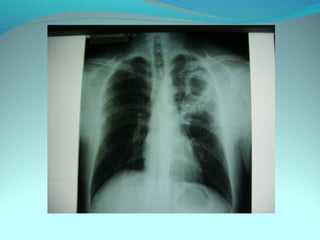

Opacité triangulaire a base cardiaque a sommet

axillaire dense et homogène

Par ailleurs on note

Une opacité plus dense que celle arrondie de 3cm de

diam hilaire gauche ;une surélévation de la coupole

diaphragmatique gauche é poche a aire gastrique

DIAGNOSTIC :

ADP hilaire gauche avec trouble de ventilation

Surelevation de la coupole G et de la poche gastrique

avec de clarté le médiastin

DIAGNOSTIC:

Hernie diaphragmatique paralysie du diaphragme